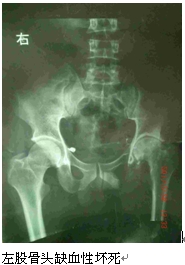

病症有脑中风、高血压、糖尿病、头痛、腰背痛、肩颈痛、坐骨神经痛、胸痛、腹痛、胃痛、感冒、咳嗽、气喘、皮肤病、耳鸣听障、眼结膜炎、阴道炎、足部静脉曲张…等。但亦有少数骨折病者因无钱医治造成骨骼生长畸形、功能障碍,及许多行走困难的患者因膝关节炎肿痛及股骨头缺血性坏死、皆与爬山路有关,亦有很多女性患者发生手腕隧道症、其因苗女要耕地做粗活造成,尚有一腹肿胀已20年的60岁老妇、怀疑是卵巢囊肿(ovarian cyst) 建议做腹部B超。